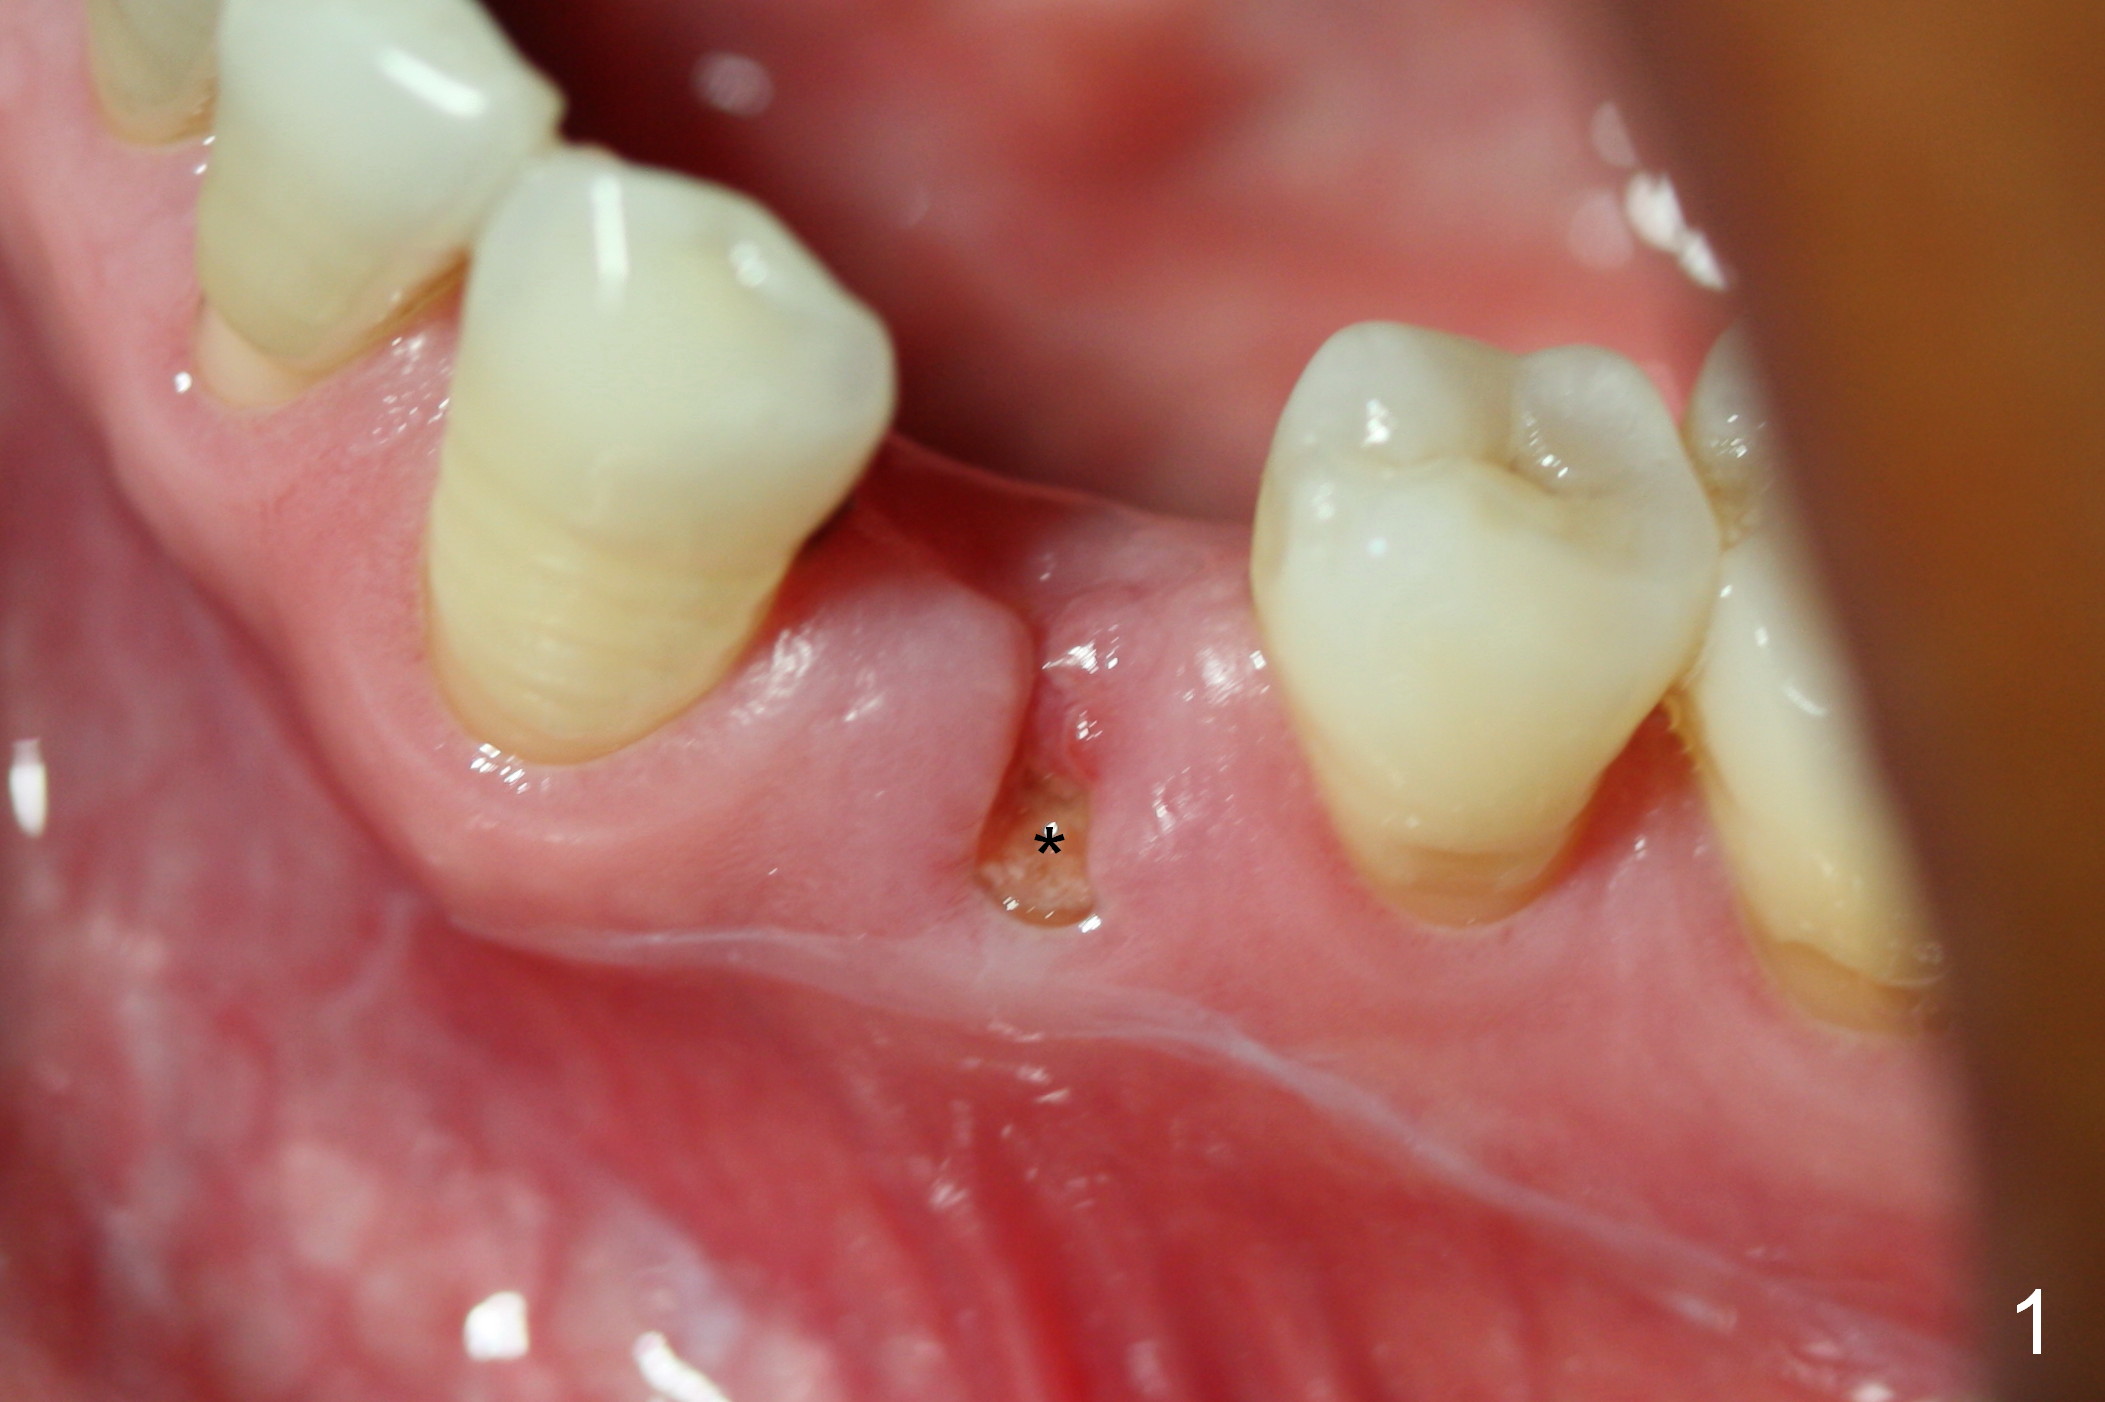

The residual root at #21 seems to be buccally positioned (Fig.1 *).  The initial osteotomy is established with the 1.6 mm drill at 11 mm (Fig.2).  Later the depth increases to 13 mm.  The initial osteotomy is found to be too lingual, but experience shows that as osteotomy increases in diameter, the trajectory would shift buccally due to the thick lingual plate (slope).  When 3.3 mm Magic drill reaches 11 mm, the patient feels pain.  It is probably due to the dense bone.  A 4x11 mm IBS implant cannot be seated due to high torque; it is removed.  The osteotomy is increased with 3.8 mm drill.  The implant is re-seated with >55 Ncm; it is over-lingually placed.  Due to failure to seat the implant driver completely, the implant cannot be un-torqued.  A 4.5 mm 15° angled abutment (3 mm cuff) is placed for immediate provisional (Fig.3,4 *).